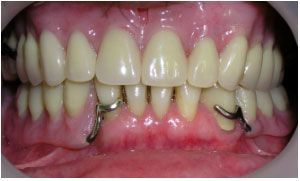

На нижнюю челюсть был изготовлен бюгельный протез на кламерах с выраженной металлической язычной частью. На верхнюю челюсть бюгельный протез был изготовлен с литой небной частью и с использованием скрытых удерживающих замков. У клыков были срезаны коронковые части зубов и в место них установлены корневые культевые вкладки с замковыми элементами. Благодаря этому жевательная нагрузка равномерно распределяется и воздействие на оставшиеся опорные зубы минимально, так как основная нагрузка приходится на слизистую альвеолярного отростка верхней челюсти.

Окончательный вид протеза